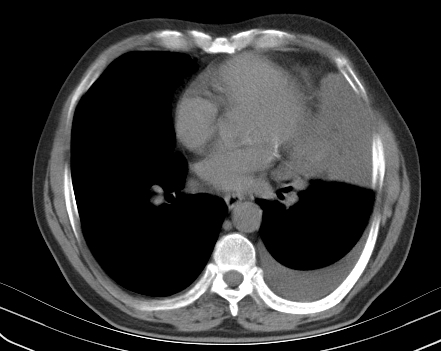

以下是引用老爱克斯新网客在2008-7-31 6:30:00的发言:[br]左肺上叶大片状病灶,左肺上叶支气管狭窄呈鼠尾状,左肺门增大,纵隔内见肿大淋巴结,左侧胸腔积液,余肺清晰。左肺中心型肺癌淋巴结转移,

以下是引用zjb在2008-7-31 6:32:00的发言:[br]左侧中心性肺癌 阻塞性肺炎 肺不张 胸腔积液 建议气管镜

以下是引用zjzjr在2008-7-31 8:45:00的发言:[br]考虑左侧中心性肺癌伴阻塞性肺炎,左肺上叶肺不张,纵隔淋巴结转移;左侧胸腔积液。建议行纤支镜检查。

以下是引用sdzyy在2008-7-31 8:47:00的发言:[br]病灶较治疗前有所进展,胸水增多, 左侧中心性肺癌 并 阻塞性肺炎 肺不张 胸腔积液 可能性大; 建议气管镜检查。 [br] [br]